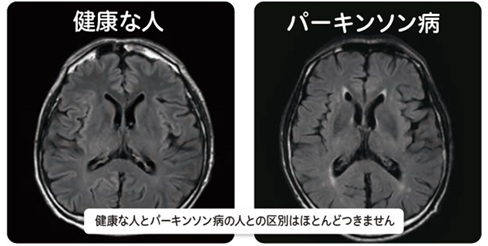

パーキンソン症候群の頭部MRI

上段:本態性振戦,薬剤性パーキンソニズム,SWEDDs,AD,

下段:PD,MSA,PSP,DLB

SWEDDs= scan without evidence of dopaminergic deficits